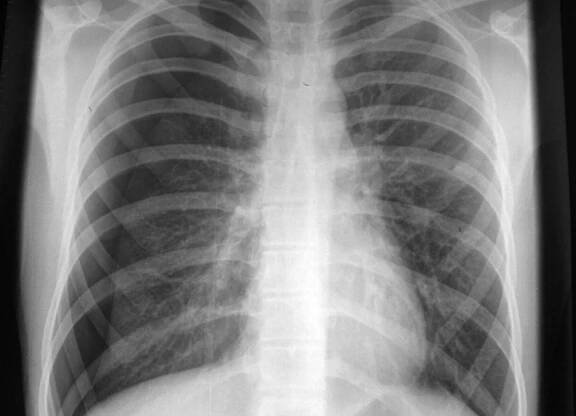

Rentgenový snímek – pneumotorax levé plíce a nahromadění vzduchu v pleurální dutině hrudníku (bílá barva). Zdroj: Getty Images